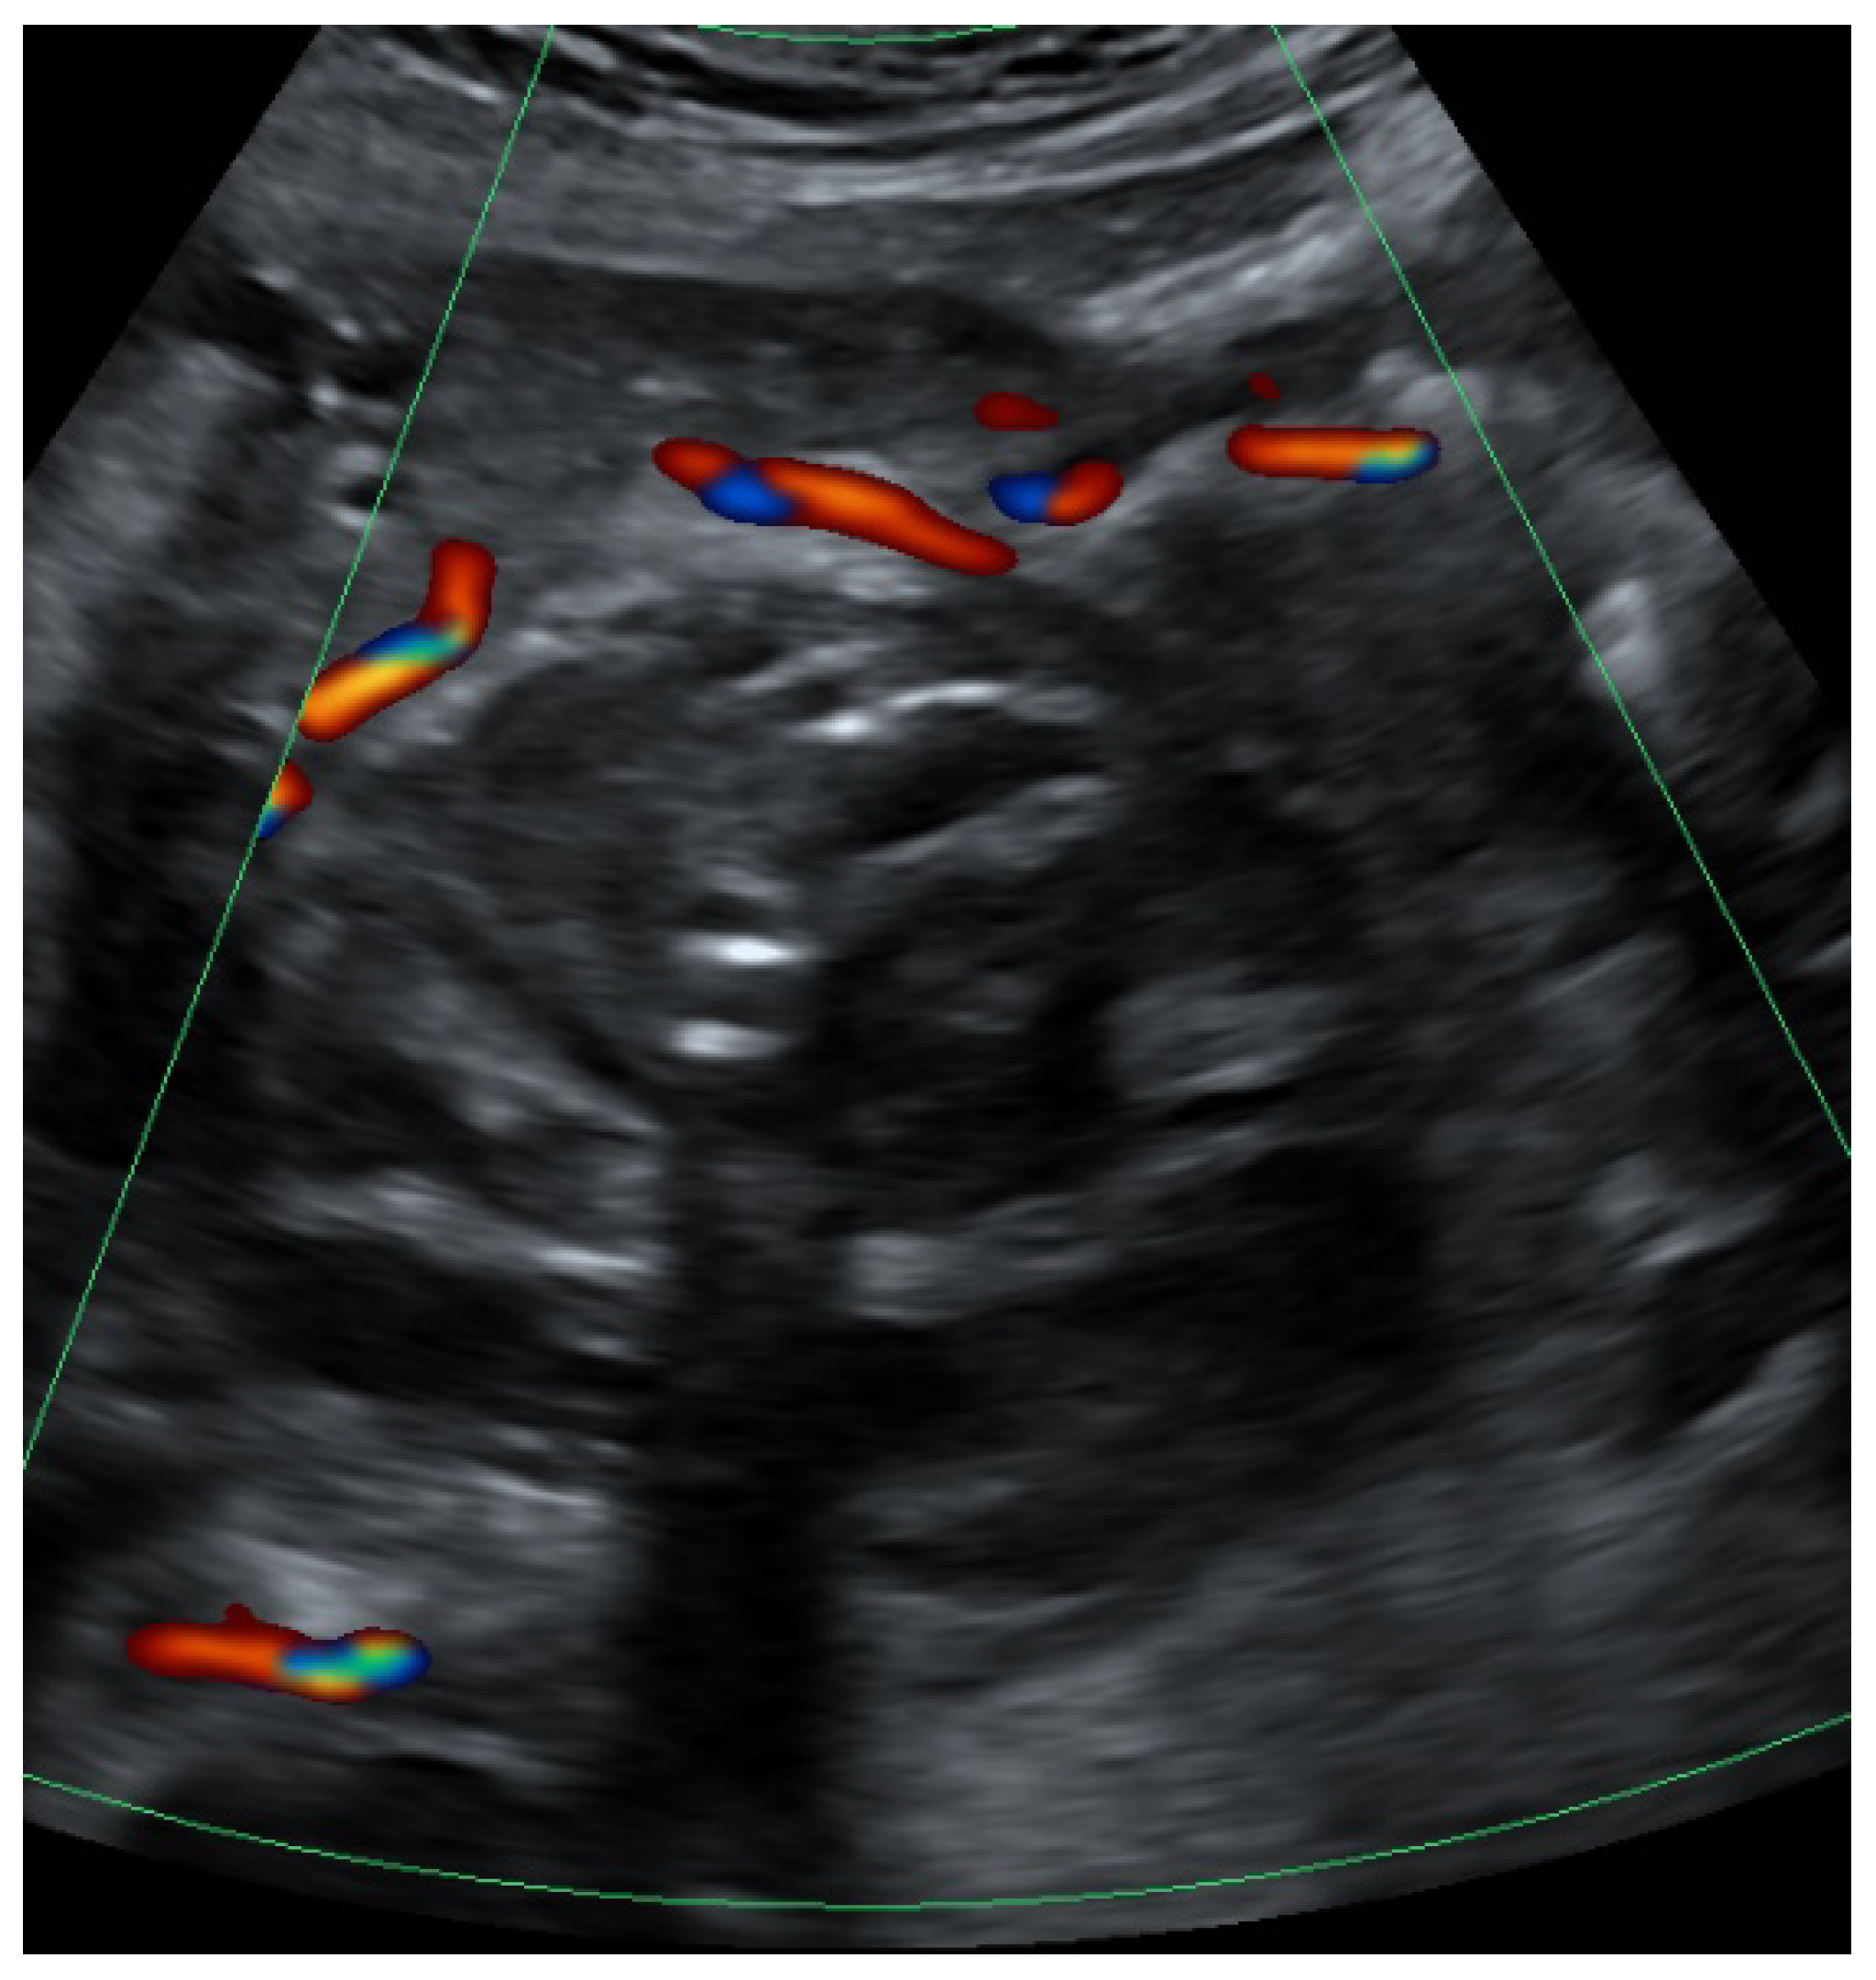

When presenting in our clinic, there were no signs of circulatory compromise (blood pressure 115/73 mmHg, pulse 72 bpm), no fever and no vaginal bleeding. Hemoglobin was 10.4 g/dL on the day of the new admission, and leucocyte levels were 7.3 G/l and 12.5 G/l, respectively. There was no free fluid in the abdominal cavity on transabdominal ultrasound. There was a pressure pain over the lower right abdomen with discrete guarding. An acute abdomen was ruled out. Upon transvaginal ultrasound, however, there was an echogenic mass of 8.6 cm in diameter on the right side, adjacent to the uterus, with a double-headed anechoic structure in the center, each cavity of approximately 3–4 cm in diameter. Color Doppler revealed a swirl of colors (Yin–Yang sign) and a pulse-synchronous blood flow from one cavity to the other as in arterial perfusion (Figure 1a–c).

UAP is a rare cause of delayed postpartum hemorrhage, it occurs in approximately in 2–3/1000 births [2]. In contrast to the mainly seeping bleeding after a caesarean section, a ruptured UAP usually results in acute, life-threatening bleeding, uterine, vaginal and/or intra-abdominal, after a seemingly uncomplicated initial postoperative period. Unlike a true aneurysm, a pseudoaneurysm does not have all three layers of the arterial wall. The differential diagnosis of a pseudoaneurysm includes acquired arteriovenous malformations (AVM), arteriovenous fistulas and direct vessel ruptures [3]. UAPs usually develop after iatrogenic damage to the vessel wall, after which there is an outflow of blood into the periarterial tissue, leading to the formation of a blood-filled cavity with surrounding hematoma communicating with the parent arterial lumen. The abovementioned Yin–Yang sign representing turbulent blood flow within the cavity as well as the to-and-fro pattern are sonographic signs suggestive of UAP [4,5].

Figure 1. (a) Ultrasound findings in B-mode showing an anechoic lesion within an echogenic mass representing the UAP with surrounding hematoma. (b) Color Doppler showing Yin–Yang sign (between arrows). (c) Pulsed wave Doppler showing a to-and-fro pattern in the lower part of the image.